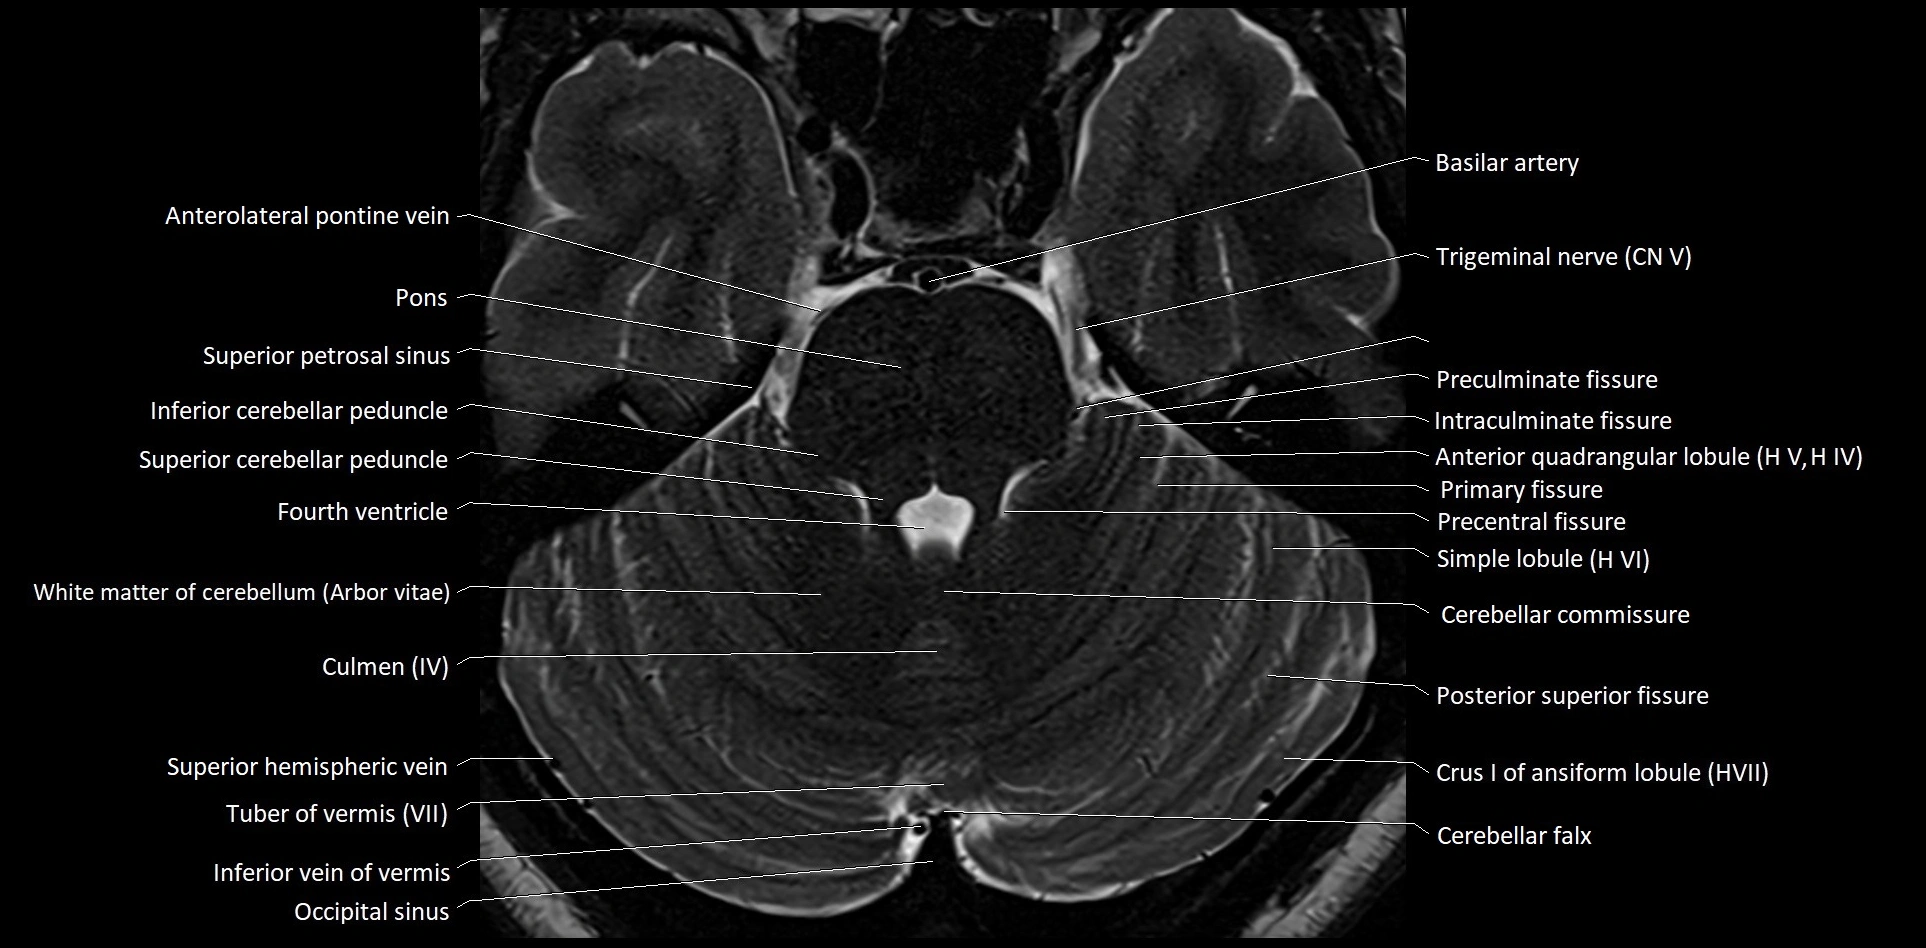

- Anterolateral pontine vein

- Arbor Vitae (Cerebellar White Matter)

- Cerebellar commissure

- Cerebellar falx

- Culmen

- Inferior cerebellar peduncle

- Inferior vein of vermis

- Intraculminate fissure

- Occipital sinus

- Preculminate fissure

- Primary fissure

- Simple lobule

- Superior cerebellar peduncle

- Superior petrosal sinus

- Trigeminal nerve (Cranial nerve V)

- White matter of cerebellum (Arbor vitae)